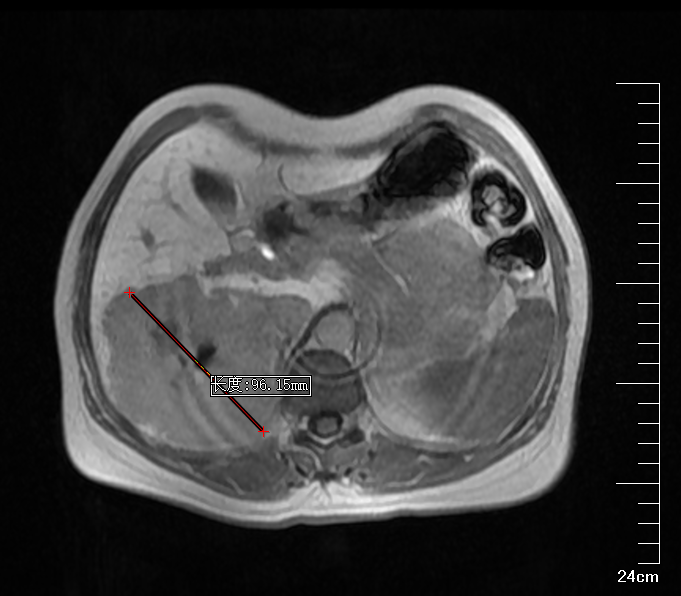

肝胆胰外科古松钢副主任在查看患者及外院CT报告后,认为患者右肝巨大肿物,大小约9*10*9.5cm,考虑为肝右后叶巨大血管瘤,需积极行手术治疗,否则血管瘤有破裂出血可能。将钱女士收治入院后,进一步完善腹部增强CT,评估患者肝储备功能以及心肺功能。

图片 2.png